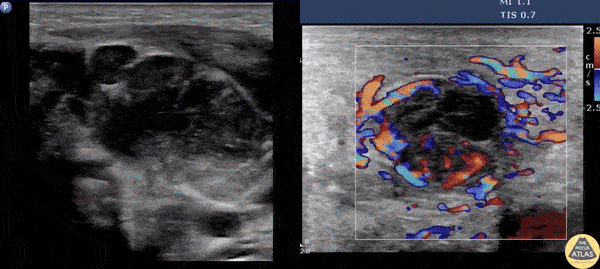

Soft Tissue - Suppurative Lymphadenitis

A male presents with a left neck mass that is erythematous and edematous with a prior history of MRSA. Contemplating incision and drainage, ultrasound was switched to doppler flow. Doppler revealed increased flow surrounding an inner hypoechoic region suggesting suppurative lymphadenitis. Because of this, I & D was not indicated, and differential includes necrosis/hemorrhage into metastatic node. Image courtesy of Robert Jones DO, FACEP @RJonesSonoEM Director, Emergency Ultrasound; MetroHealth Medical Center; Professor, Case Western Reserve Medical School, Cleveland, OH View his original post here